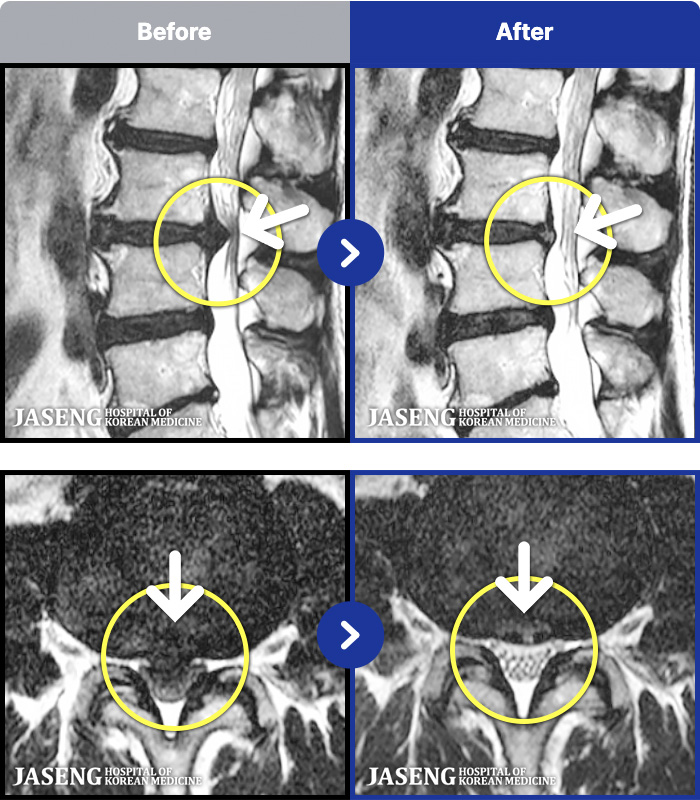

MRI ġ

1,237 MRI ũ ʸ Ȯϼ.